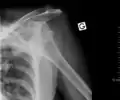

Anterior dislocation of the left shoulder. | |

A shoulder dislocation often occurs as a result of a fall onto an outstretched arm or onto the shoulder.[3] Diagnosis is typically based on symptoms and confirmed by X-rays.[2] They are classified as anterior, posterior, inferior, and superior with most being anterior.[2][1]

A diagnosis of shoulder dislocation is often suspected based on the person's history and physical examination. Radiographs are made to confirm the diagnosis. Most dislocations are apparent on radiographs showing incongruence of the glenohumeral joint. Posterior dislocations may be hard to detect on standard AP radiographs, but are more readily detected on other views. After reduction, radiographs are usually repeated to confirm successful reduction and to detect bone damage. After repeated shoulder dislocations, an MRI scan may be used to assess soft tissue damage. In regards to recurrent dislocations, the apprehension test (anterior instability) and sulcus sign (inferior instability) are useful methods for determining predisposition to future dislocation.

In over 95% of shoulder dislocations, the humerus is displaced anteriorly.[8] In most of those, the head of the humerus comes to rest under the coracoid process, referred to as sub-coracoid dislocation. Sub-glenoid, subclavicular, and, very rarely, intrathoracic or retroperitoneal dislocations may also occur.[9]